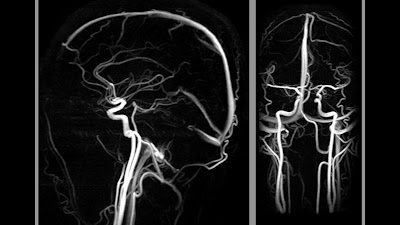

Εάν ένα ανεύρυσμα αιμορραγήσει, ο ασθενής σχεδόν πάντα έχει έναν ξαφνικό και δυνατό πονοκέφαλο («σαν σφυριά») που προτρέπει τον ασθενή για να επιδιώξει την ιατρική φροντίδα. Μια εξέταση με αξονική τομογραφία εγκεφάλου προσδιορίζει συνήθως το αίμα έξω από τα αγγεία δηλ την αιμορραγία, η οποία ονομάζεται υπαραχνοειδής αιμορραγία (SAH). Η αγγειογραφία (DSA) είναι η καλύτερη εξέταση για να προσδιορίσει το συγκεκριμένο αγγείο στο οποίο βρίσκεται το ανεύρυσμα που έχει αιμορραγήσει και φαίνεται η λεπτομερής ανατομία του ανευρύσματος.

Περιστασιακά, τα ανευρύσματα αυξάνονται και πιέζουν την περιβάλλουσα περιοχή του εγκεφάλου και προκαλούν άλλα συμπτώματα όπως ο πονοκέφαλος ή διπλωπία ( καθώς και μια σειρά άλλων συμπτωμάτων ). Η Μαγνητική Τομογραφία εγκεφάλου και η Μαγνητική αγγειογραφία μπορούν να προσδιορίσουν ένα τέτοιο ανεύρυσμα που δεν έχει αιμορραγήσει.